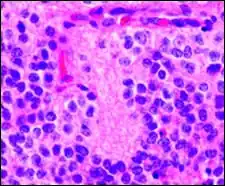

Micrograph of Homer-Wright pseudorosettes

A Homer-Wright pseudorosette is a type of pseudorosette in which differentiated tumor cells surround the neuropil.[15] Examples of tumors containing these are neuroblastoma, medulloblastoma, pinealoblastoma, and primitive neuroectodermal tumors of bone. Homer-Wright rosettes are considered "pseudo" in the sense that they are not true rosettes. Unlike Flexner–Wintersteiner rosettes, which contain an empty lumen, Homer-Wright rosettes contain abundant fibrillary material. They are named for James Homer Wright.